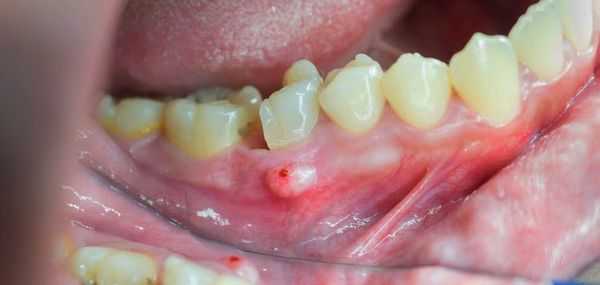

По клиническому течению выделяют 4 последовательные стадии заболевания. На нулевом этапе признаки некротических изменений в челюсти отсутствуют, определяются лишь неспецифические пародонтальные симптомы. Больные жалуются на шаткость и патологическую подвижность зубов, дискомфорт во время еды. В редких случаях на поверхности десны образуется свищевой ход.

На первой стадии заболевания определяется частично обнаженная челюстная кость либо глубокий свищевой ход, который достигает костной поверхности. В пределах альвеолярного отростка возможны очаговые рентгенологические изменения. Переход остеонекроза на вторую клиническую стадию происходит в момент присоединения инфекции к существующим участкам деструкции челюсти. Возникают мучительные боли, затруднения приема пищи.

После острой стадии наступает подострая. На десне образуется гнойничок или свищ, через который гнойные выделения и воспалительная жидкость выходят наружу.